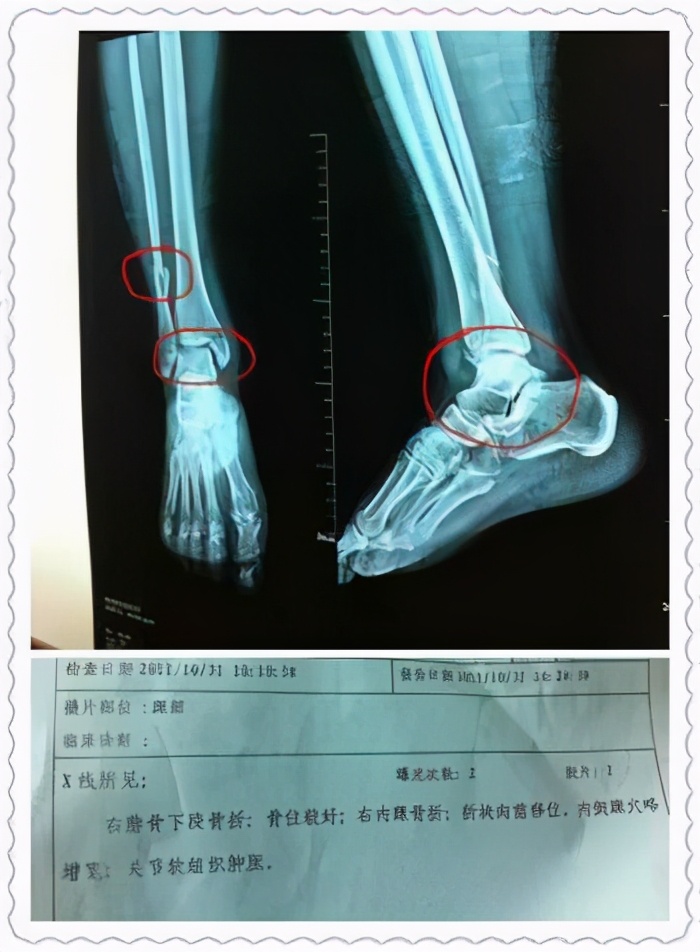

2、骨折术后:在我们科,一部分脚踝骨折的病人,术后反应脚脖子路走得多就爱肿,这就是涉及关节骨折的最主要的术后并发症,创伤性关节炎。骨折术后的病人,康复是至关重要的,比如踝关节骨折的病人,我经常让患者做的一个动作就是勾脚,既有利于较重,还能有效的防治关节的僵硬,关于这方面的知识我以后还会详细的介绍,一些骨折术后的朋友可以关注我。